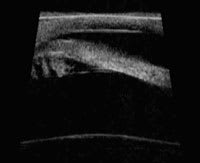

Model MHF: A high-frequency ultrasound of the anterior chamber angle and ciliary body. |

Portable ultrasound

You can think of the portable ultrasonic device (Model MHF-1, Portable Ophthalmic Devices Inc.) as a portable version of the existing ultrasound biomicroscopy (UBM, Carl Zeiss Meditec) technology that uses a high-frequency transducer on the surface of the eye.

The Zeiss UBM and new version of the MHF-1 operate at 50MHz and can produce images with good resolution and a depth of penetration of the ocular tissue (4-5mm in depth). This is an advantage over the anterior segment OCT counterparts, which do not image as deeply.

This technology may improve imaging of conditions that occur behind the iris, such as tumors and the position of posterior chamber intraocular lenses, which may contribute to the pathogenesis of various forms of glaucoma. The Model MHF-1 portable ultrasonic device should receive approval from the FDA, for use in humans, in the near future.